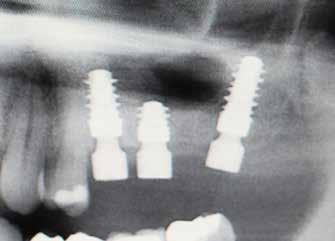

bukkális 1. kép: Kiindulási állapot, 2020. január. 3. kép: Kiindulási CBCT felvétel. 2. kép: Kiindulási állapot a palatinális oldal felől.

6. kép: Implantátum-ágy preparáció. 7. a–b. képek: Implantátum behelyezés. 8. kép: A behelyezett implantátum. 10. a–b képek: Azonnali ideiglenes korona készítése. 9. kép: Megfelelő primer stabilitás.

12. kép: A 6 hónapos intraorális kontrollröntgen felvétele.